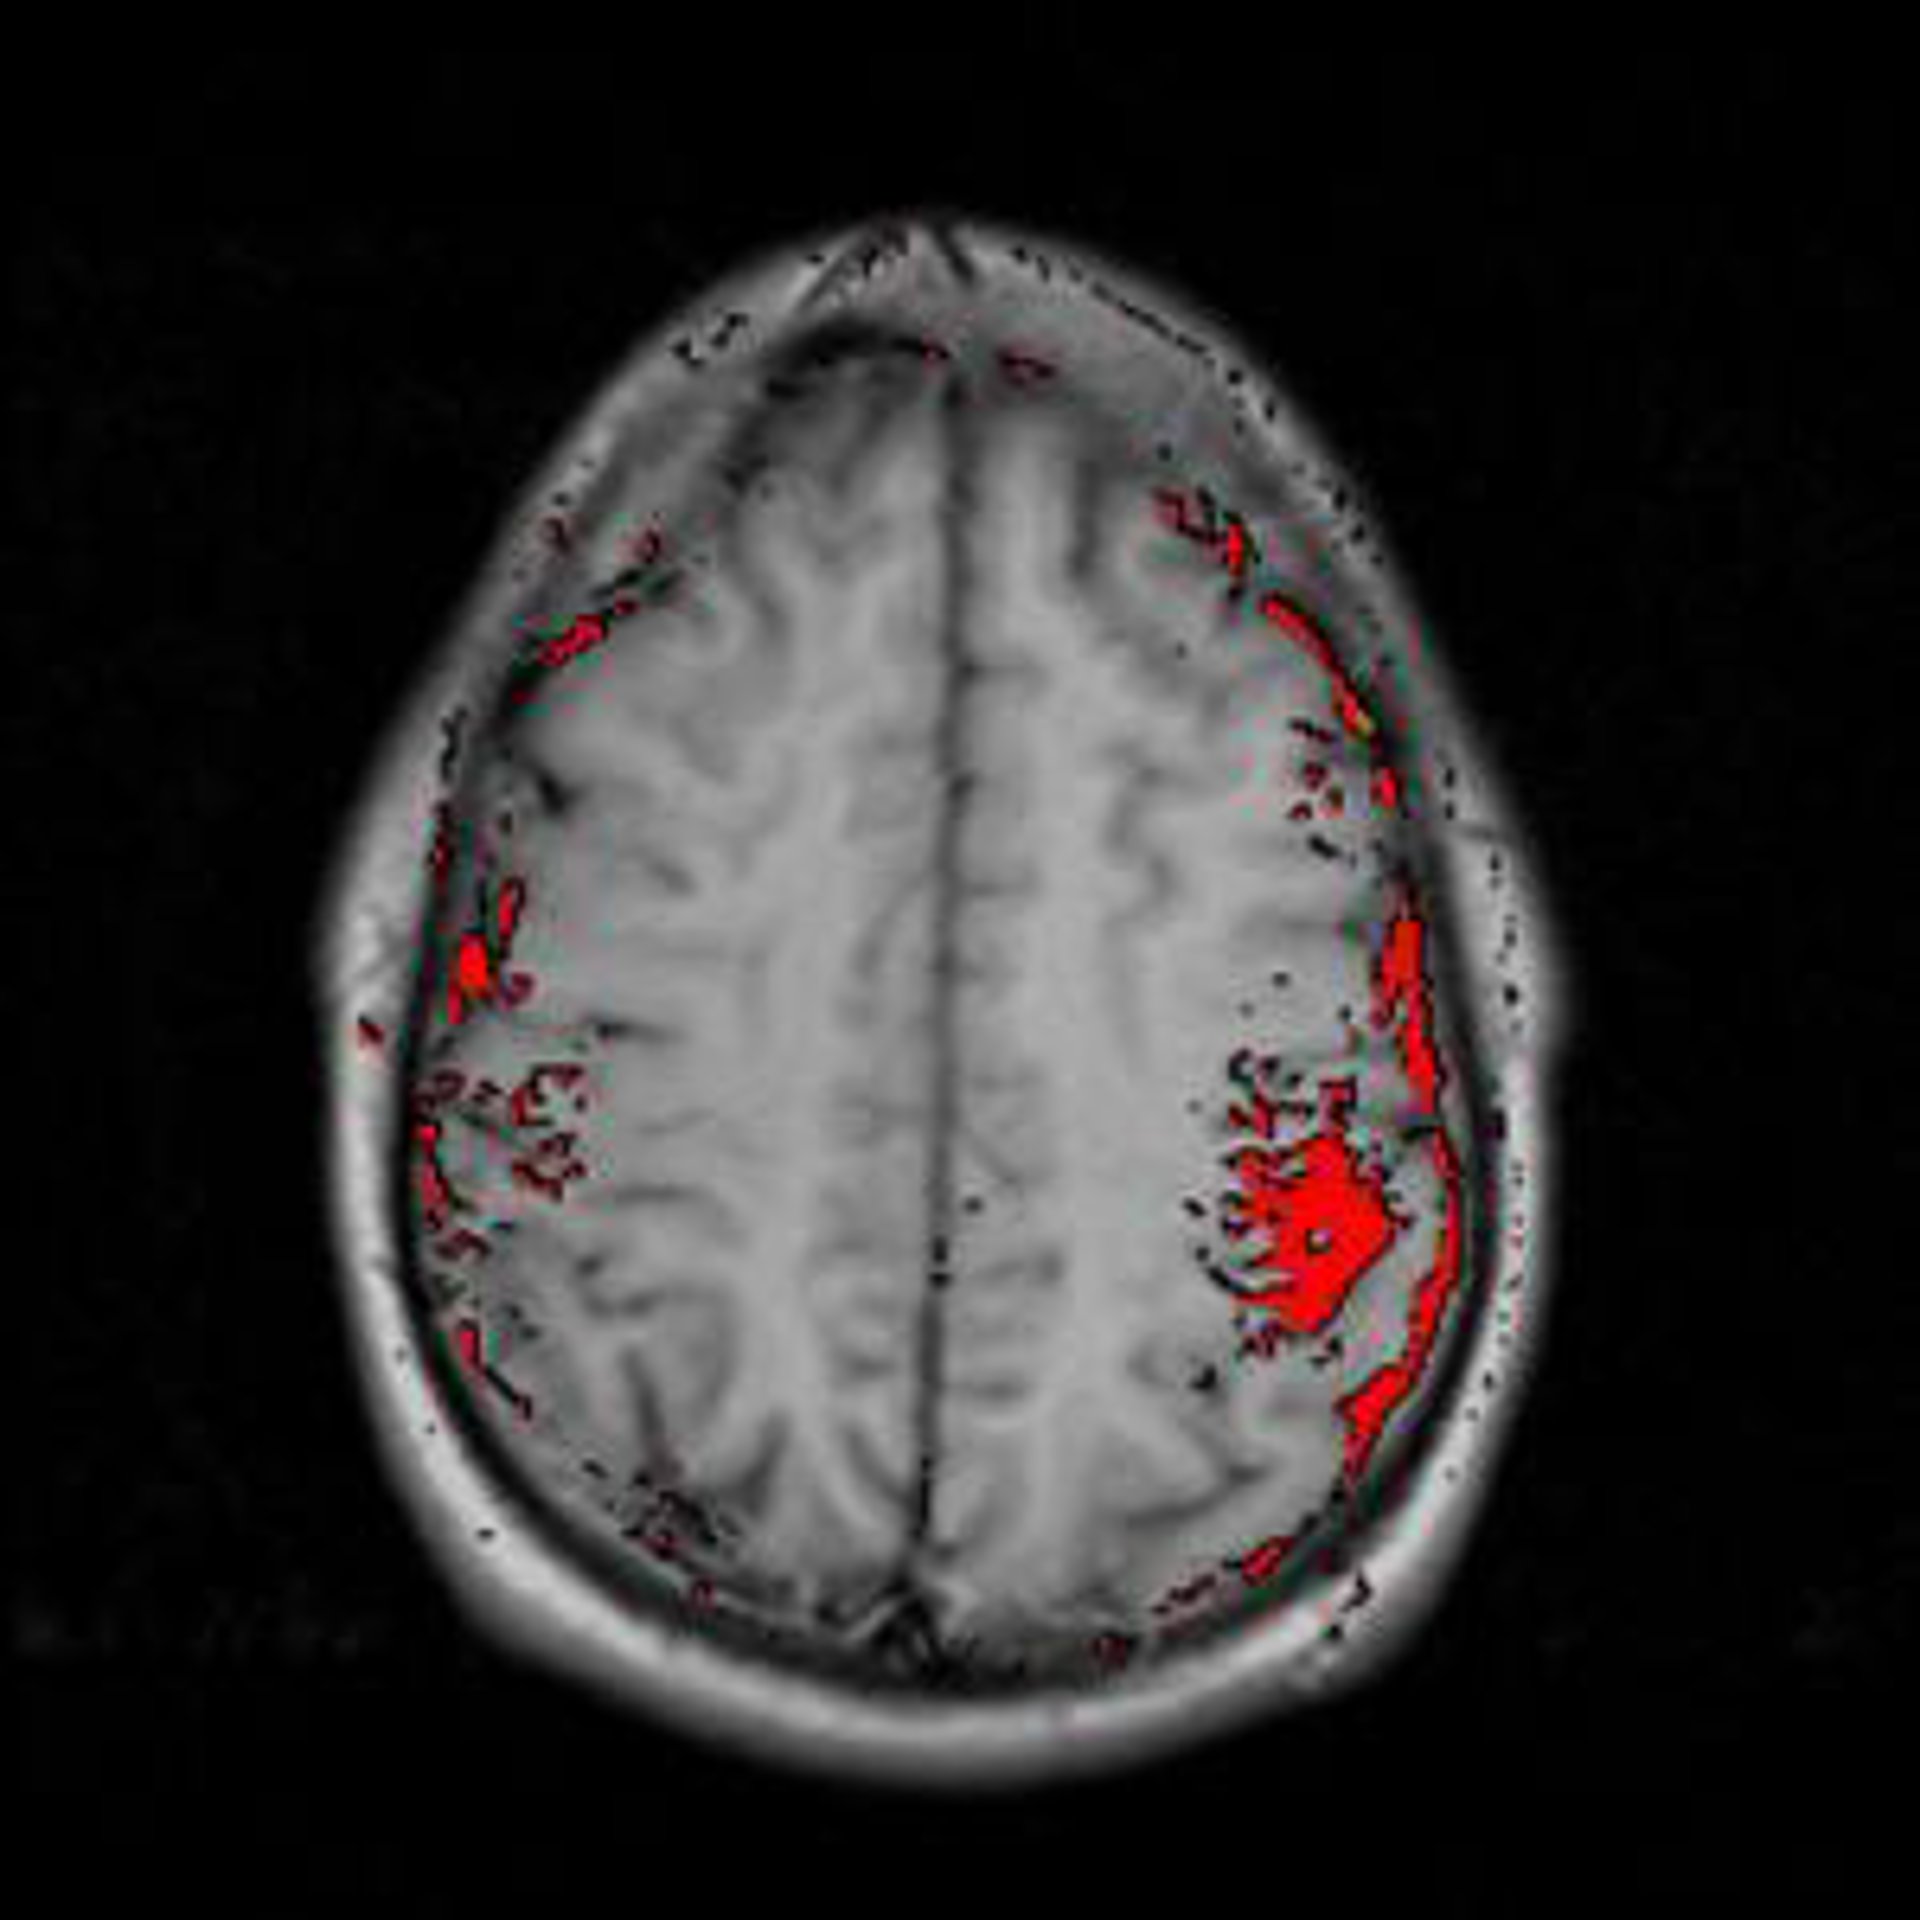

Investigadores del Consejo Superior de Investigaciones Científicas (CSIC) han descubierto un nuevo modelo de almacenamiento celular de información en el cerebro. Los resultados, publicados hoy en la revista 'Science', demuestran que los astrocitos, un tipo de células de glía al que durante más de un siglo se le ha asignado sólo una función pasiva de soporte neuronal, están directamente involucrados en la transmisión y almacenamiento de información en el sistema nervioso.

"Ahora, cuando estudiemos las bases celulares de la actividad cerebral, no bastará con hablar sólo de neuronas, habremos de tener en cuenta también a los astrocitos", señala. En concreto, el estudio revela que los astrocitos del hipocampo, una región cerebral implicada en procesos de memoria y aprendizaje, pueden liberar un mensajero químico, el glutamato, que aumenta de forma transitoria, durante decenas de segundos, la eficacia de la transmisión nerviosa entre las neuronas.

Para obtener estos resultados, los investigadores utilizaron muestras de cerebro de rata, y se combinaron técnicas de electrofisiología y biología celular.

"Con el uso simultáneo de tres microelectrodos, se ha podido estimular una única sinapsis, registrar su actividad desde la neurona postsináptica y registrar y estimular selectivamente un único astrocito adyacente a esta sinapsis", expone el investigador.